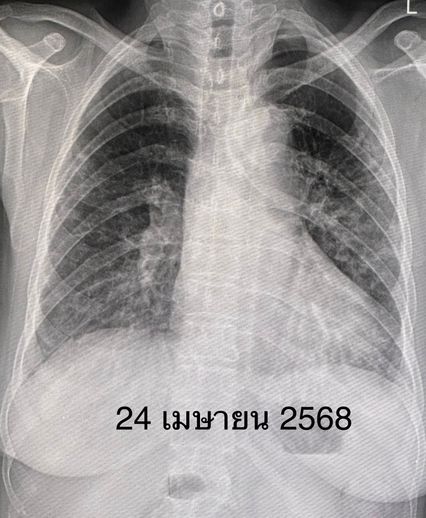

หลังได้รับยา คนไข้เหนื่อยน้อยลง ระดับออกซิเจนที่ปลายนิ้วดีขึ้น ใช้ออกซิเจนแบบหนวดกุ้งธรรมดาทางจมูก ไม่ต้องใช้ High-Flow nasal O2 cannula เอกซเรย์ปอดดีขึ้นช้า ๆ ลุกขึ้นเดินได้ ระดับโซเดียมในเลือดเกือบปกติ กลับบ้านได้หลังจากรักษาอยู่ในโรงพยาบาล 15 วัน หมอนัดติดตามเป็นคนไข้นอกต่อไป